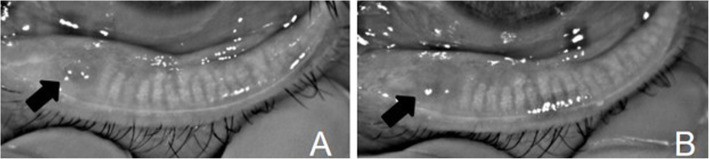

Changes in the acinar structure in the chalazion area

In this study, we intended to observe the acinar structure in the chalazion area at the cellular level. However, due to the limitation of current ophthalmic in vivo LSCM [13, 14], clear acinar images can be obtained only at or near the eyelid margin. In our study, only 3 patients (3 eyelids) with conservative treatment had chalazia located near the eyelid margin, and in vivo LSCM examination revealed a large number of inflammatory cells in the chalazion area before treatment. At 1 month after complete chalazion resolution, no obvious inflammatory cells were present, but the intact acinar structure was not found at the area. (Fig. 4).

Fig. 4.

In vivo confocal microscopy images in chalazion area before and after treatment. a shows a large number of inflammatory cells in the chalazion area before treatment; b shows incomplete acinar structure in the range of meibomian gland loss at 1 months after chalazion resolution. c shows normal acinar structure of meibomian gland

In this study, only 3 patients had a chalazion located near the eyelid margin, and the intact acinar structure was not found at the area after complete chalazion resolution. The reason for this result may be that the meibomian gland is a special type of sebaceous gland with a holocrine acinar secretion pattern, indicating that the contents of the whole glandular cells form the meibum. Normally, the basal layer of meibocytes in the periphery of the acinus contains a proliferating progenitor cell population that constantly gives rise to new meibocytes, and the above process is repeated [3]. However, when inflammatory cells infiltrate the gland, new meibocytes cannot be formed in the short term; therefore, the complete acinar structure was not observed in the chalazion area. However, this result does not indicate that new meibocytes will never regenerate. A previous study reported stem cells of the meibomian glands located at the circumference of each acinus, which were responsible for the continuous generation of meibocytes; approximately 13 days is required for newly formed meibocytes to eventually shed in the mouse meibomian gland [27]. Perhaps due to the effects of inflammation, new meibocytes need more time to regenerate. Moreover, another study showed that the meibomian gland can regenerate with meibomian gland probing [28]. Therefore, whether meibocytes can regenerate and the regeneration time after chalazion resolution require further study.